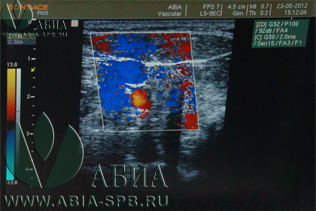

Выполняя УЗИ сосудов головы и шеи в нашей клинике, вы получаете на руки заключение врача, в котором отражены результаты комплексной оценки сосудов головы и шеи. У нас выполняется дуплекс / триплекс сосудов головы и шеи, который позволяет выявить изменения внутри и снаружи сосуда, рассмотреть его геометрию, толщину стенок, наличие даже самых минимальных внутрипросветных изменений, а также оценить степень воздействия на сосуды окружающих структур снаружи. Это наиболее информативное обследование сосудов на настоящий момент. Только дуплексное / триплексное исследование сосудов головы и шеи дает полную комплексную оценку сосудов, внутрипросветных изменений, а также, характера и скорости кровотока.

Дуплекс / триплекс сосудов головы и шеи даёт врачу-неврологу полную картину о состоянии сосудов и позволяет изучить их анатомию. Во время исследования врач определяет: